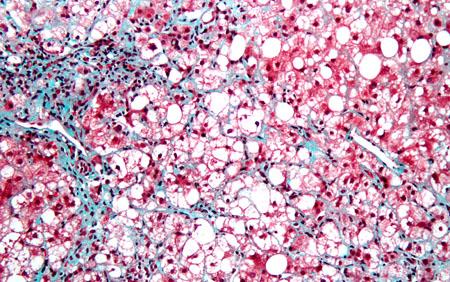

Researchers at the University of California, San Diego School of Medicine say that hepatic fibrosis, which involves scarring of the liver that can result in dysfunction and, in severe cases, cirrhosis and cancer, may be as much a consequence of genetics as environmental factors.

"The most common known causes of hepatic fibrosis have been viral hepatitis C infections, alcohol abuse, poor diet and obesity and nonalcoholic steatohepatitis or NASH, which resembles alcoholic liver disease but occurs in people who drink little or no alcohol," said first author Rohit Loomba, MD, associate professor of clinical medicine in the Division of Gastroenterology. "We found, however, that hepatic fibrosis and steatosis (infiltration of liver cells with fat) are strong genetic traits. At around 50 percent heritability, they're more genetic than body mass index."

Using two advanced magnetic resonance imaging techniques that quantify fat content in the liver and liver stiffness (a measure of fibrosis), the researchers found that 26 of the 120 participants had nonalcoholic fatty liver disease (NAFLD), which can be a precursor to development of more serious conditions. Hepatic steatosis and liver fibrosis correlated strongly with monozygotic twins, but not with dizygotic pairs.